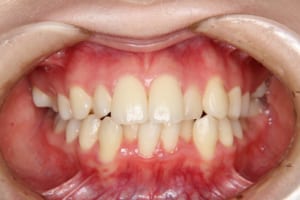

• Before

治療前

年齢・性別 19才 女性

主訴 下の歯の凸凹

上の前歯が出ているのが気になる